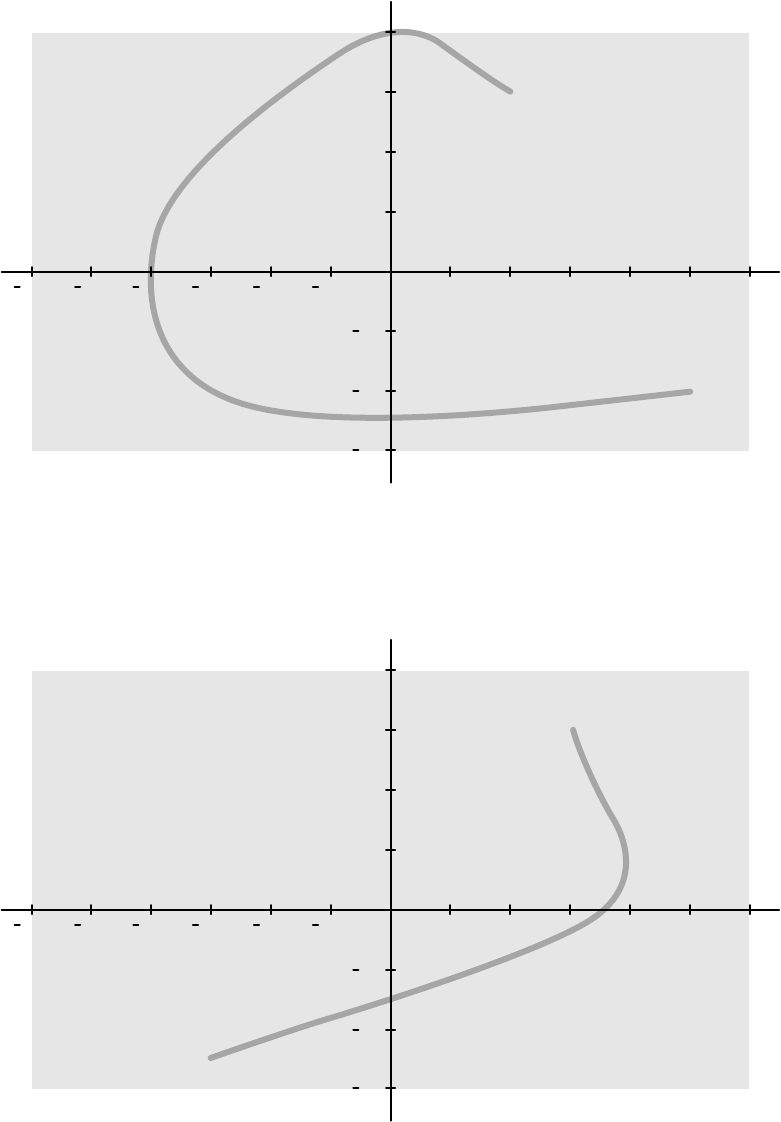

16.21.2 Mapy izokermy systemu C12/F12........................................................................ 310

16.21.3 Mapy izokermy systemu F15................................................................................ 311

16.21.4 Mapy izokermy systemu C20/F20........................................................................ 312